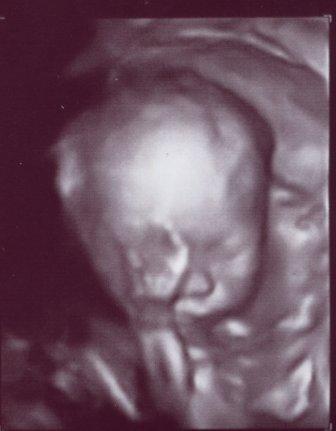

ich hab mal unser Süsse in 3D eingescannt.. schaut mal, wie toll das aussieht!

LG